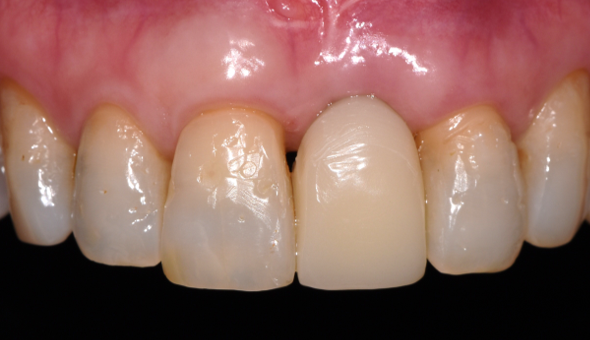

잇몸이식의 효과로 오른쪽 위 앞니 뿌리도 덮어져 시술 전보다 앞니의 외형이 많이 좋아졌습니다.

기존 치아사이 공간도 오른쪽 윗니 치아에 레진이라는 치과 재료를 통해 치아 모양을 예쁘게 만들어 주었고

임플란트 치아 보철도 심미적인 균형을 맞추어 치료를 완료했습니다.